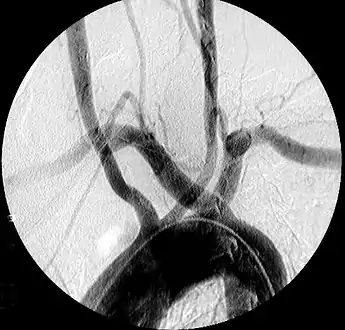

| Aberrant subclavian artery on MR angiography. | |

Aberrant right subclavian artery at angiography.